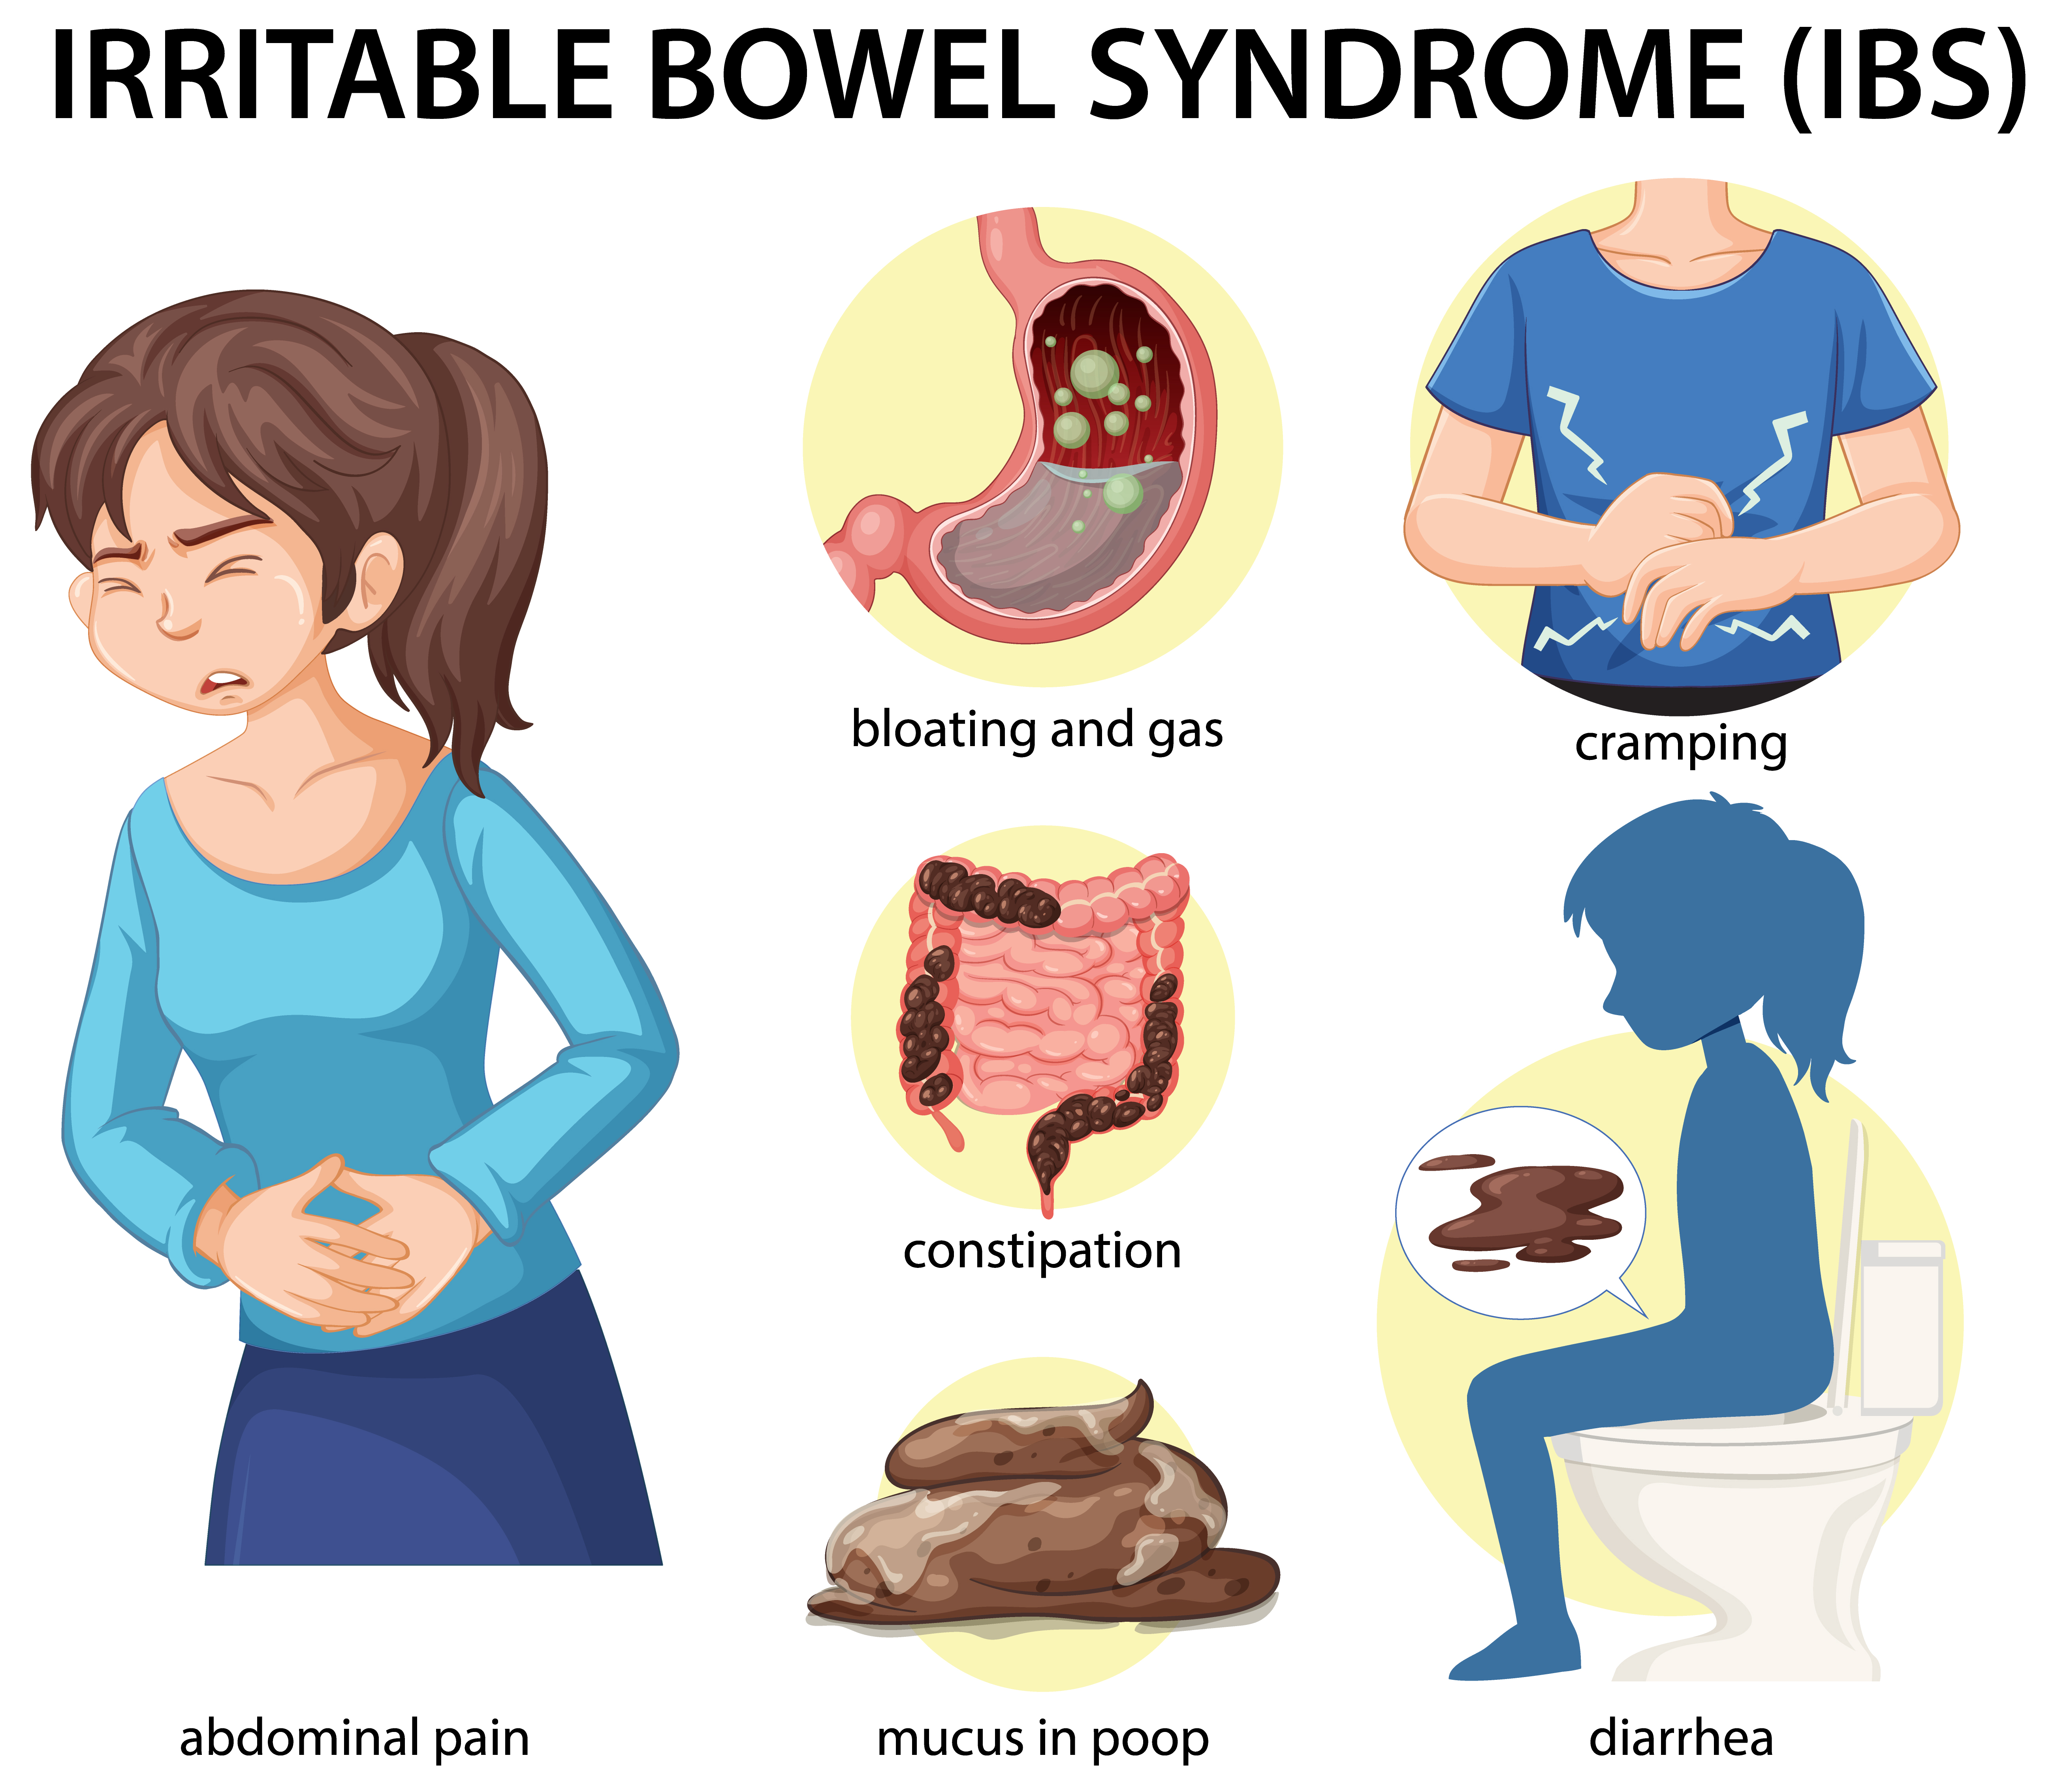

Diarrhea

Diarrhea is a condition characterized by the frequent passage of loose, watery stools. It can be acute, lasting a short period, or chronic, persisting for weeks.

After rain havoc, dengue, diarrhoea threat looms; experts advise caution

Revolutionary Diarrhea Prevention Program